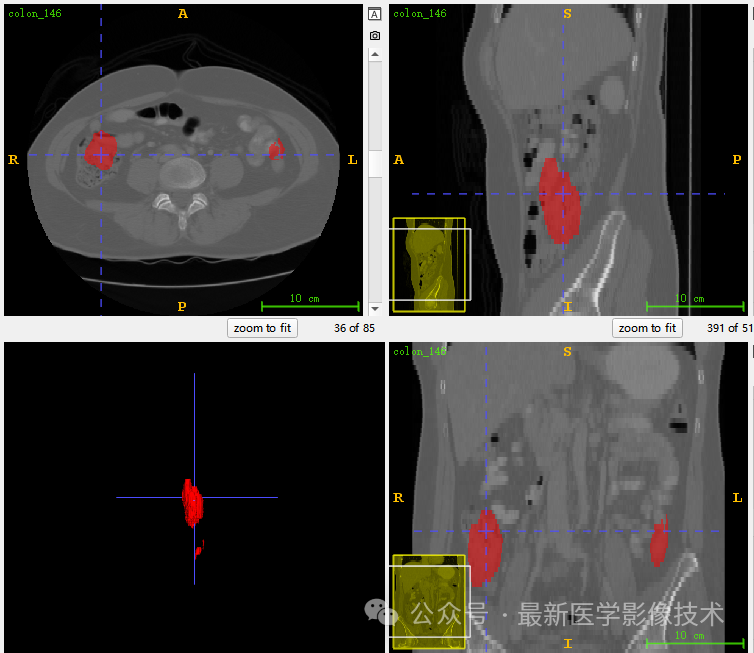

5、验证集分割结果

左图是金标准结果,右图是预测结果。